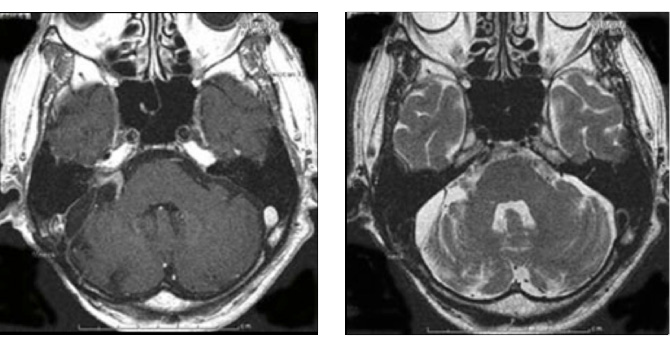

図2:80歳男性 歩行障害をきたした大型神経鞘種

(左図)治療前MRI:顕著な脳の圧迫と脳浮腫を認める

(左図)術後2年後のMRI:薄い残存腫瘍をみとめるが再増大なく、脳の圧迫は改善している

また高齢者でも手術は有益です。図2の症例は80歳の男性症例ですが、10年来右耳難聴で聴神経腫瘍の診断はつけられておりましたが、治療希望せず放置されておりました。しかし歩行障害が進行し当院に紹介されてまいりました。

造影MRIでは大型の腫瘍を認め、周囲の脳幹や小脳が強く圧迫され腫れています。手術にて90%の腫瘍摘出を行い、脳の圧迫もとれ、症状も改善し、治療後3年たった現在でも元気で外来に通っていらっしゃいます。